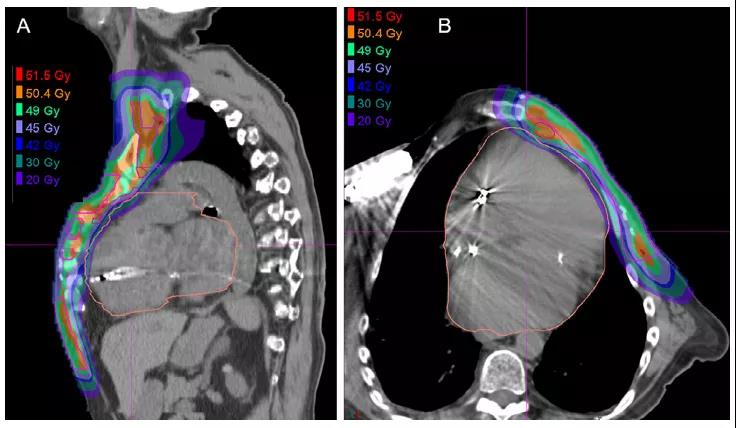

現(xiàn)代光子放療對于全乳照射通常可以提供很好的正常組織保護。然而,劑量學研究表明,質子治療有改善靶區(qū)覆蓋和減少對心臟和肺的劑量的潛力,包括完全或接近完全的心臟保護。正常組織保護的絕對改善可能在具有復雜解剖結構的患者(如漏斗胸或雞胸)、瘤床位于內側和無法進行心臟保護的患者中最為顯著,如DIBH或俯臥位(圖5)。對于活動性心肺疾病患者,正常組織保護的潛在臨床重要性可能更大。

圖5. 一例局部晚期左乳腺癌和雞胸患者(A)矢狀位和(B)橫斷位20 Gy劑量分布圖,胸部的畸形表現(xiàn)為胸骨和肋骨突出。圖片展示出盡管在不利的解剖結構下,胸壁(粉紅色)和IMN(紅色)CTV靶區(qū)的覆蓋和正常組織保護仍然很好。